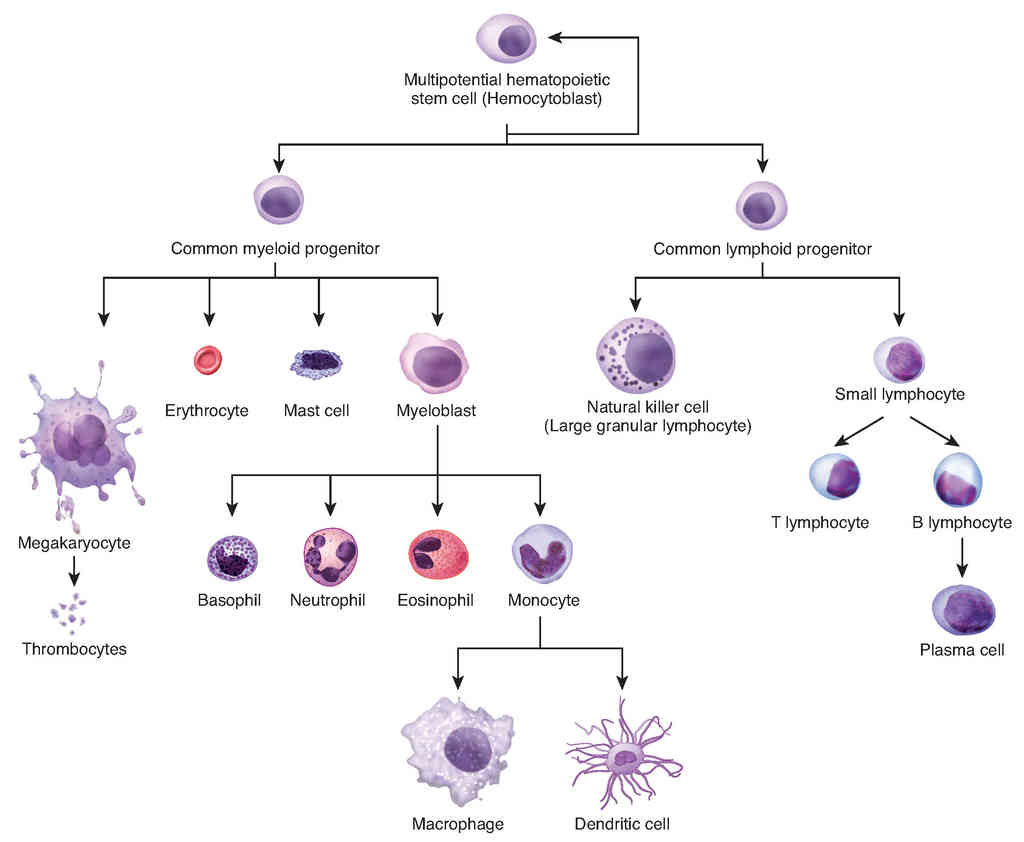

This page is under construction. For now, it is just a resource of the images found in the OpenStax Anatomy and Physiology Handbook. It wil slowly change into a revision tool. Each slide has a number. Use this to refer to the slide. When completed, it will have an unlabelled section, with labelled slides in parallel. On the unlabelled slides, write your answer and use the labelled slide to assess yourself. Keep track by also noting the number on each slide. Improvement at each attempt is important, more so than full marks on a first attempt.